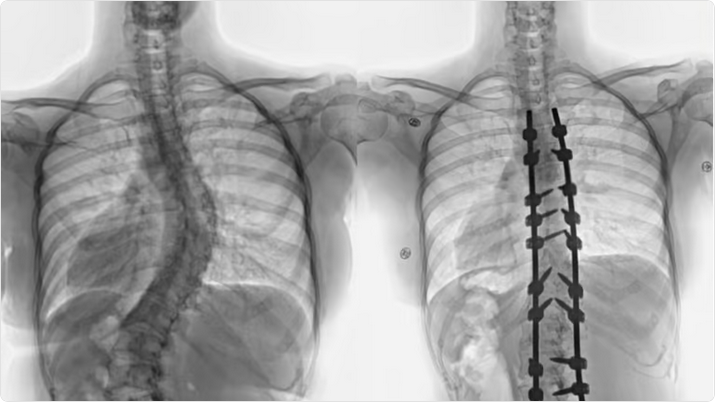

بفضل من الله تعالى وتوفيقه، أنهى مستشفى الدكتور سليمان الحبيب بالقصيم، معاناة شابة عشرينية مصابة بانحراف مضاعف ومتطور في العمود الفقري " الجنف"، إذ نجح الفريق الطبي الذي قاده د. صلاح الدين خليفة استشاري جراحة العظام والعمود الفقري، ود. هاني الجهني استشاري جراحة المخ والاعصاب، في إجراء عملية معقدة استمرت زهاء الـ"4" ساعات، لتقويم العمود الفقري وتثبيت ودمج الفقرات.

وقال د. خليفة أن المريضة راجعت المستشفى وهي تشتكي من انحناء جانبي للعمود الفقري منذ صغرها، بدأت مؤخراً تعاني من آلام بالظهر، إضافة إلى صعوبة في ممارسة الحياة الطبيعة، أدت هذه الأعراض إلى تغيير نمط حياتها والحد من حركتها، وفور وصولها إلى المستشفى أجريت لها التحاليل والفحوصات الطبية الدقيقة، التي بينت إصابتها بحالة انحراف "جنف" مضاعف بدرجة الـ"60" للفقرات الصدرية، ودرجة 50 للفقرات القطنية ودرس الفريق الطبي الحالة على ضوء نتائج الفحوصات والتحاليل، وخلص إلى ضرورة التدخل الجراحي لعلاج العيوب، والحد من المضاعفات، وبعد اتخاذ كافة التدابير الطبية اللازمة لمثل هذه الحالات المعقدة، أخضعت الشابة لعملية جراحية، تم فيها تقويم العمود الفقري بعدد "20" من البراغي والقضبان المعدنية والطعوم العظمية الصناعية وتثبيت ودمج الفقرات، واستخدمت في العملية التي استمرت لـ"4" ساعات، مع فريق تخدير متمرس ومراقبة أعصاب وفريق تمريض ماهر إضافة الى مجموعة من أحدث الأجهزة الطبية التي ساهمت مع الكوادر الطبية عالية الكفاءة والتأهيل بالمستشفى في إنجاحها.

ونقلت المريضة الى جناح التنويم بعد العملية، وبدأت حالتها في التحسن باضطراد بعد خروجها من غرفة العمليات، إذ استطاعت المشي بتوازن بعد أقل من "24" ساعة من العملية مع فريق العلاج الطبيعي المتمرس، واستعادت قدرتها على الاستلقاء والنوم على ظهرها، فضلاً عن القوام والمظهر الطبيعي، بعد تعديل وضعية الحوض والكتف، كما أن طولها مع النجاح الكبير للتعديل زاد بحدود "3" سم، وخرجت من المستشفى وهي بصحة جيدة، وتوقع أن تستعيد كامل عافيتها سريعاً مع الإنتهاء من برنامج العلاج الطبيعي.